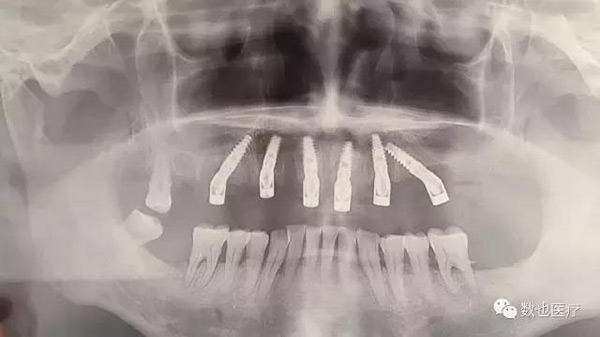

术后全景片,查看植体位置和基台就位情况